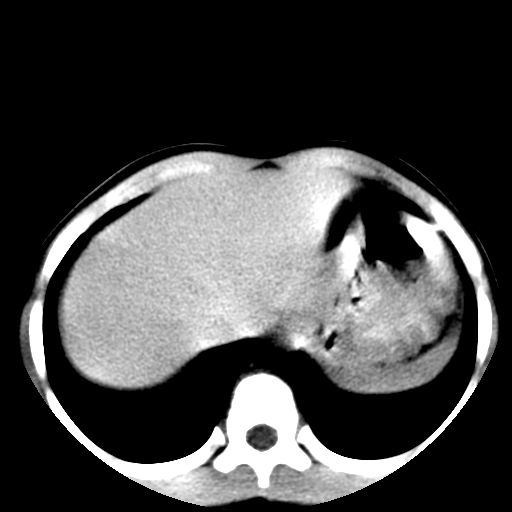

右肺多发斑片状,点条状病灶,密度不均,边界较清晰,可见点状钙化。纵隔内见多发淋巴结钙化。应该考虑肺结核可能大。反复腹痛是否有腹腔结核或肠结核?

右肺多发斑片状,点条状病灶,密度不均,边界较清晰,可见点状钙化。纵隔内见多发淋巴结钙化。应该考虑肺结核可能大。反复腹痛是否有腹腔结核或肠结核?支持!

1)右肺继发性肺结核并右肺上叶节段性肺不张,支气管扩张。2)纵隔内多发淋巴结钙化。

腹部好象未见异常。

腹部ct平扫未见明确异常

腹部ct平扫不能提示哪里有病变。